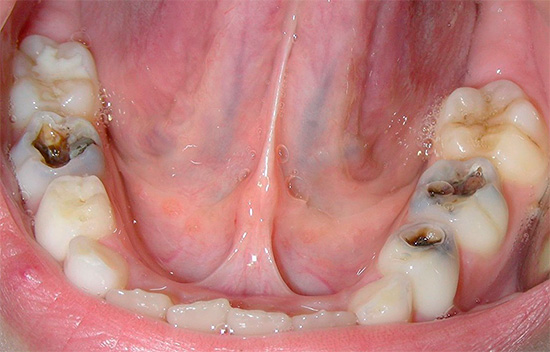

De acordo com a classificação da profundidade do processo de cárie, são distinguidos os seguintes tipos de cárie:

O último estágio do desenvolvimento do processo carioso envolve a proximidade de tecidos dentários danificados e infectados a uma polpa saudável ("nervo"). Como resultado disso, sempre existe o risco de confusão entre cáries profundas e o aparecimento de complicações na polpa de um dente quando uma infecção cariada entra nele. Portanto, nesses casos, o tratamento deve ser realizado somente após um diagnóstico detalhado da etapa do processo.

Nesse caso, a dentina amolece devido à liberação de componentes minerais (cálcio, fósforo, compostos de flúor), seguida pela dissolução da matéria orgânica (colágeno) sob a ação de enzimas bacterianas. A formação de uma cavidade como cárie média com dentina infectada amolecida, sem tratamento, leva inevitavelmente a um aprofundamento do processo patológico e a um aumento na área de destruição. Se nesta fase você não tratar cáries profundas, poderá perder tempo e haverá uma complicação na transição da infecção para tecido pulpar não protegido ("nervo") dentro do dente.